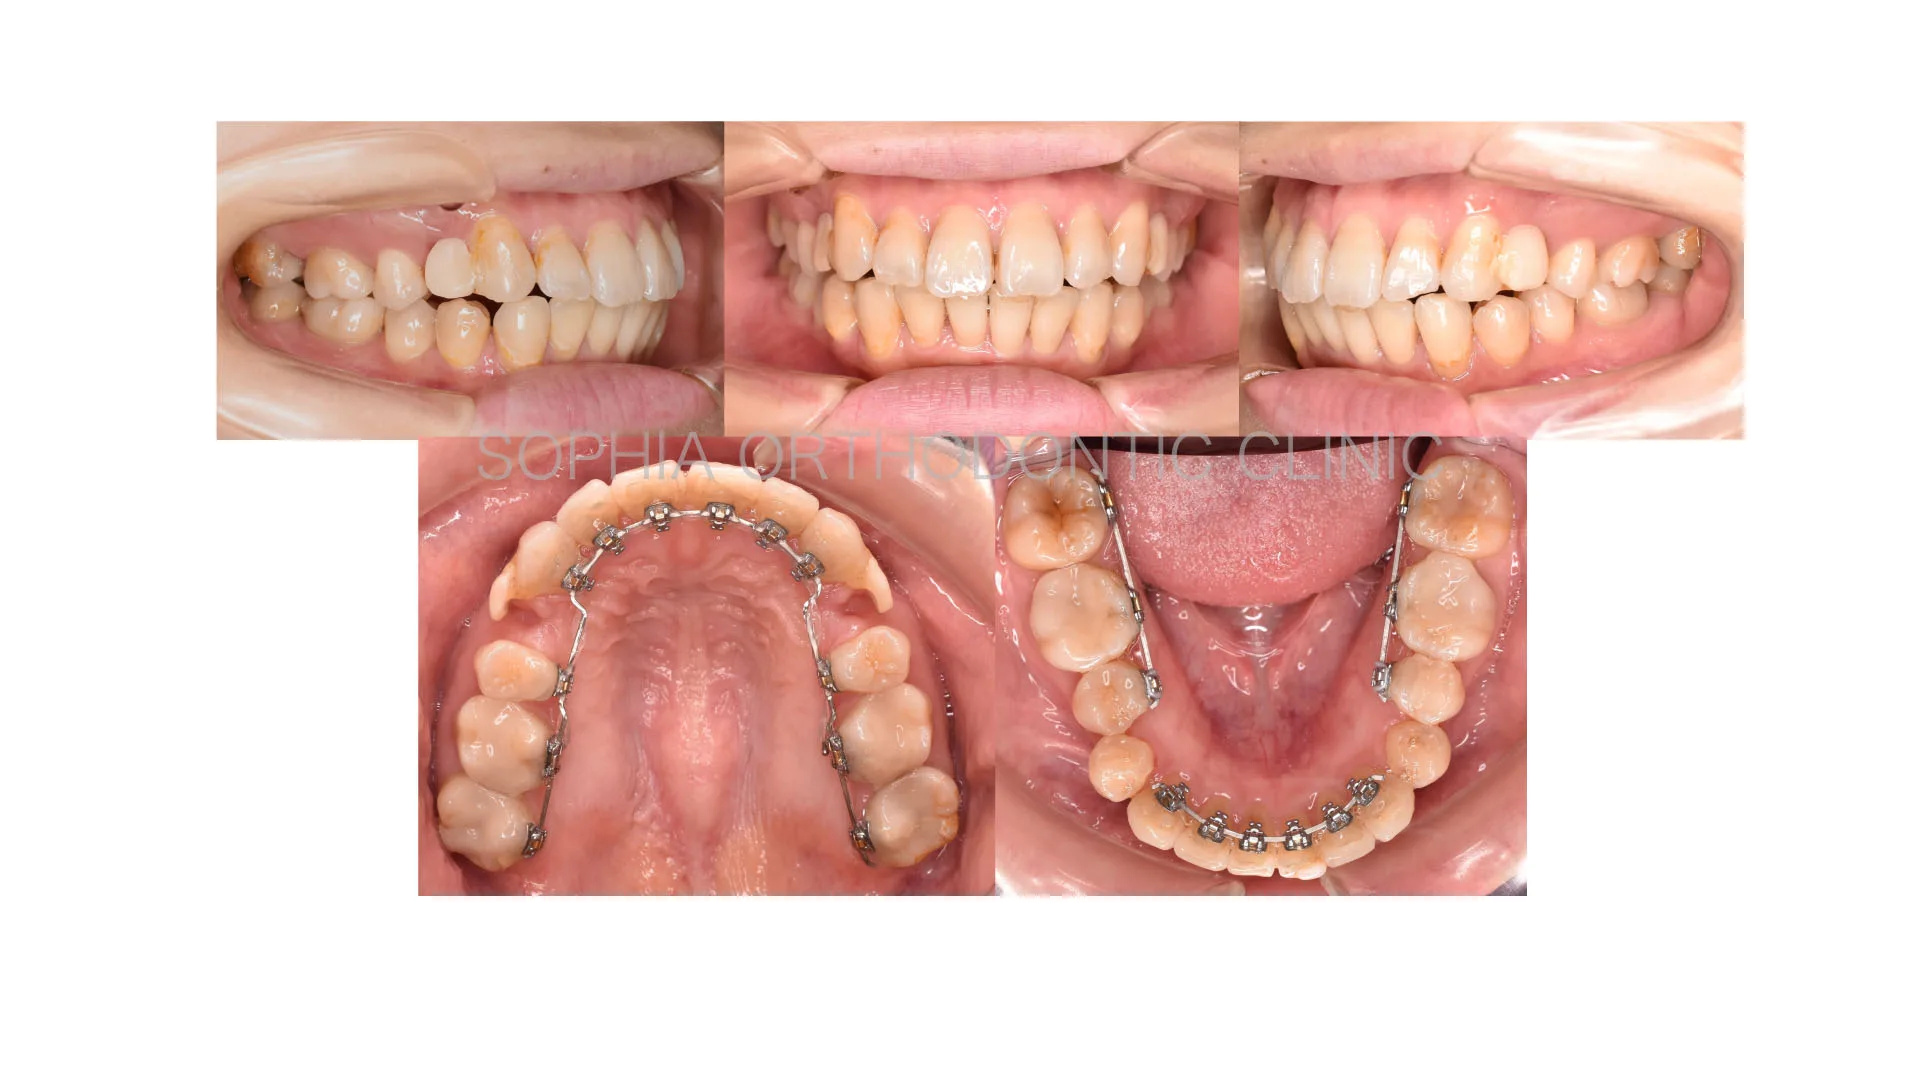

症例 前突